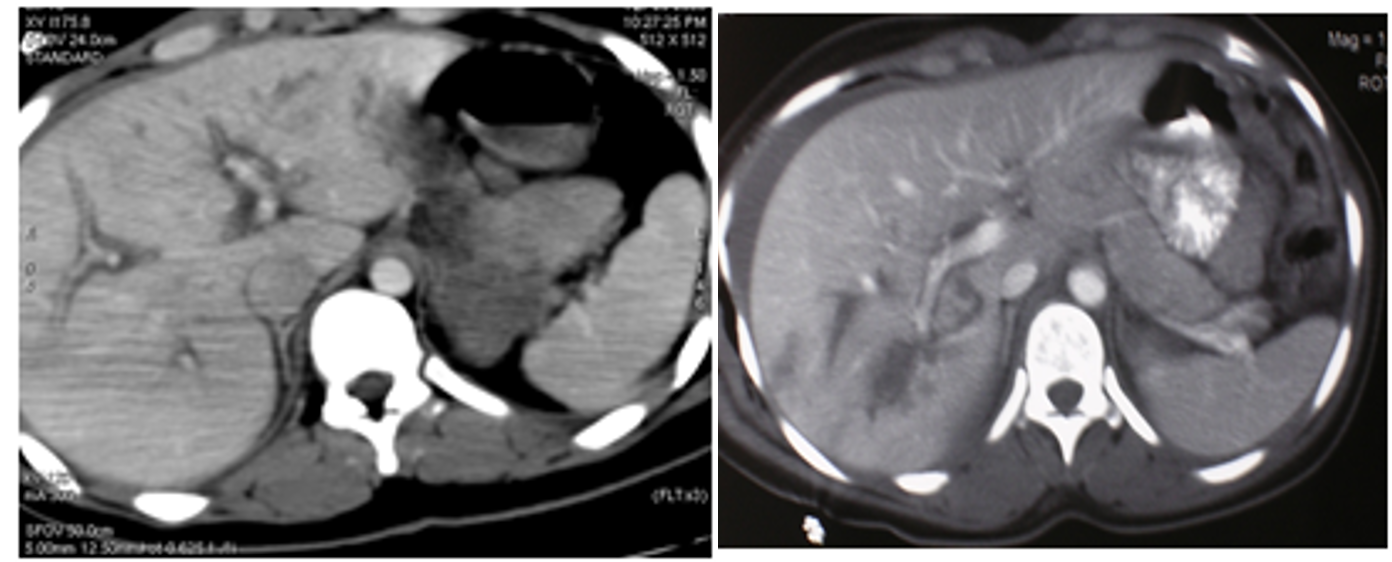

Diagnosis:

- Hemodynamically unstable- FAST

- Hemodynamically stable- FAST, CT scan

- Management based on hemodynamic status

(Image: Liver injury- CT scan)

Liver injury- Non-operative management

- Hemodynamically stable patients

- CT scan

- If No other indications for abdominal exploration

- ICU admission for close observation

- Serial hemoglobin estimation

- Transfusion requirements of <2 units of blood

- Surgery- if become unstable